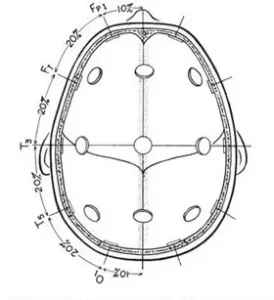

Lateral measurement of the central coronal plane strats at the left preauricular point thrugh the C vertex mark to the right preauricular point (fig.2). A mark is placed at 10% of this measurement over the preauricular points and labeled T.

The expression T represents the temporal area. Marks are then located at 20% of the lateral measurement and labeled left and right C, and the C vertex location is crossed.

Fig.3 Superior view with cross section of skull through the temporal line of electrodes illustrating the 10-20 system applied in this direction as described in the text

Antero-posterior measurements are taken from the left and right Fp position through the lateral C position to the left and right O position. This measurement is then divided equally by 25% marks and labeled lateral F, lateral C, and lateral P. Anterior coronal measurements are taken from the left and right inferior frontal position through the midline F position and divided into 25% segments, making crosses at the left lateral frontal, F vertex and right lateral frontal positions. A posterior coronal measurement is taken from the left posterior temporal mark through the midline P position and this is also divided into 25% segments and marks are labeled left lateral P, midline P and right lateral P (fig.4)

These measurements provided for the location of 19 of the 21 electrodes used in the 10-20 electrode system (fig.5). The remaining two electrodes were placed on the ear loves and labeled auricular electrodes. The electrode positions were named in anatomical terms for the cortical areas rocerded, with the exception of the “C” electrodes which were termed central since they were located over the central sulcus.

A numbering system was added to differentiate between left and right homologous regions, odd numbers for the left hemisphere, Fp1, F3, F7, C3, T3, P3, T5, and O1. Even numbers for the right hemisphere, Fp2, F4, F8, C4, T4, P4, T6, and O2. The original recommendation called the F, C and P vertex electrodes F0, C0, and P0, but later changed to Fz, Cz, and Pz (z for the zero).